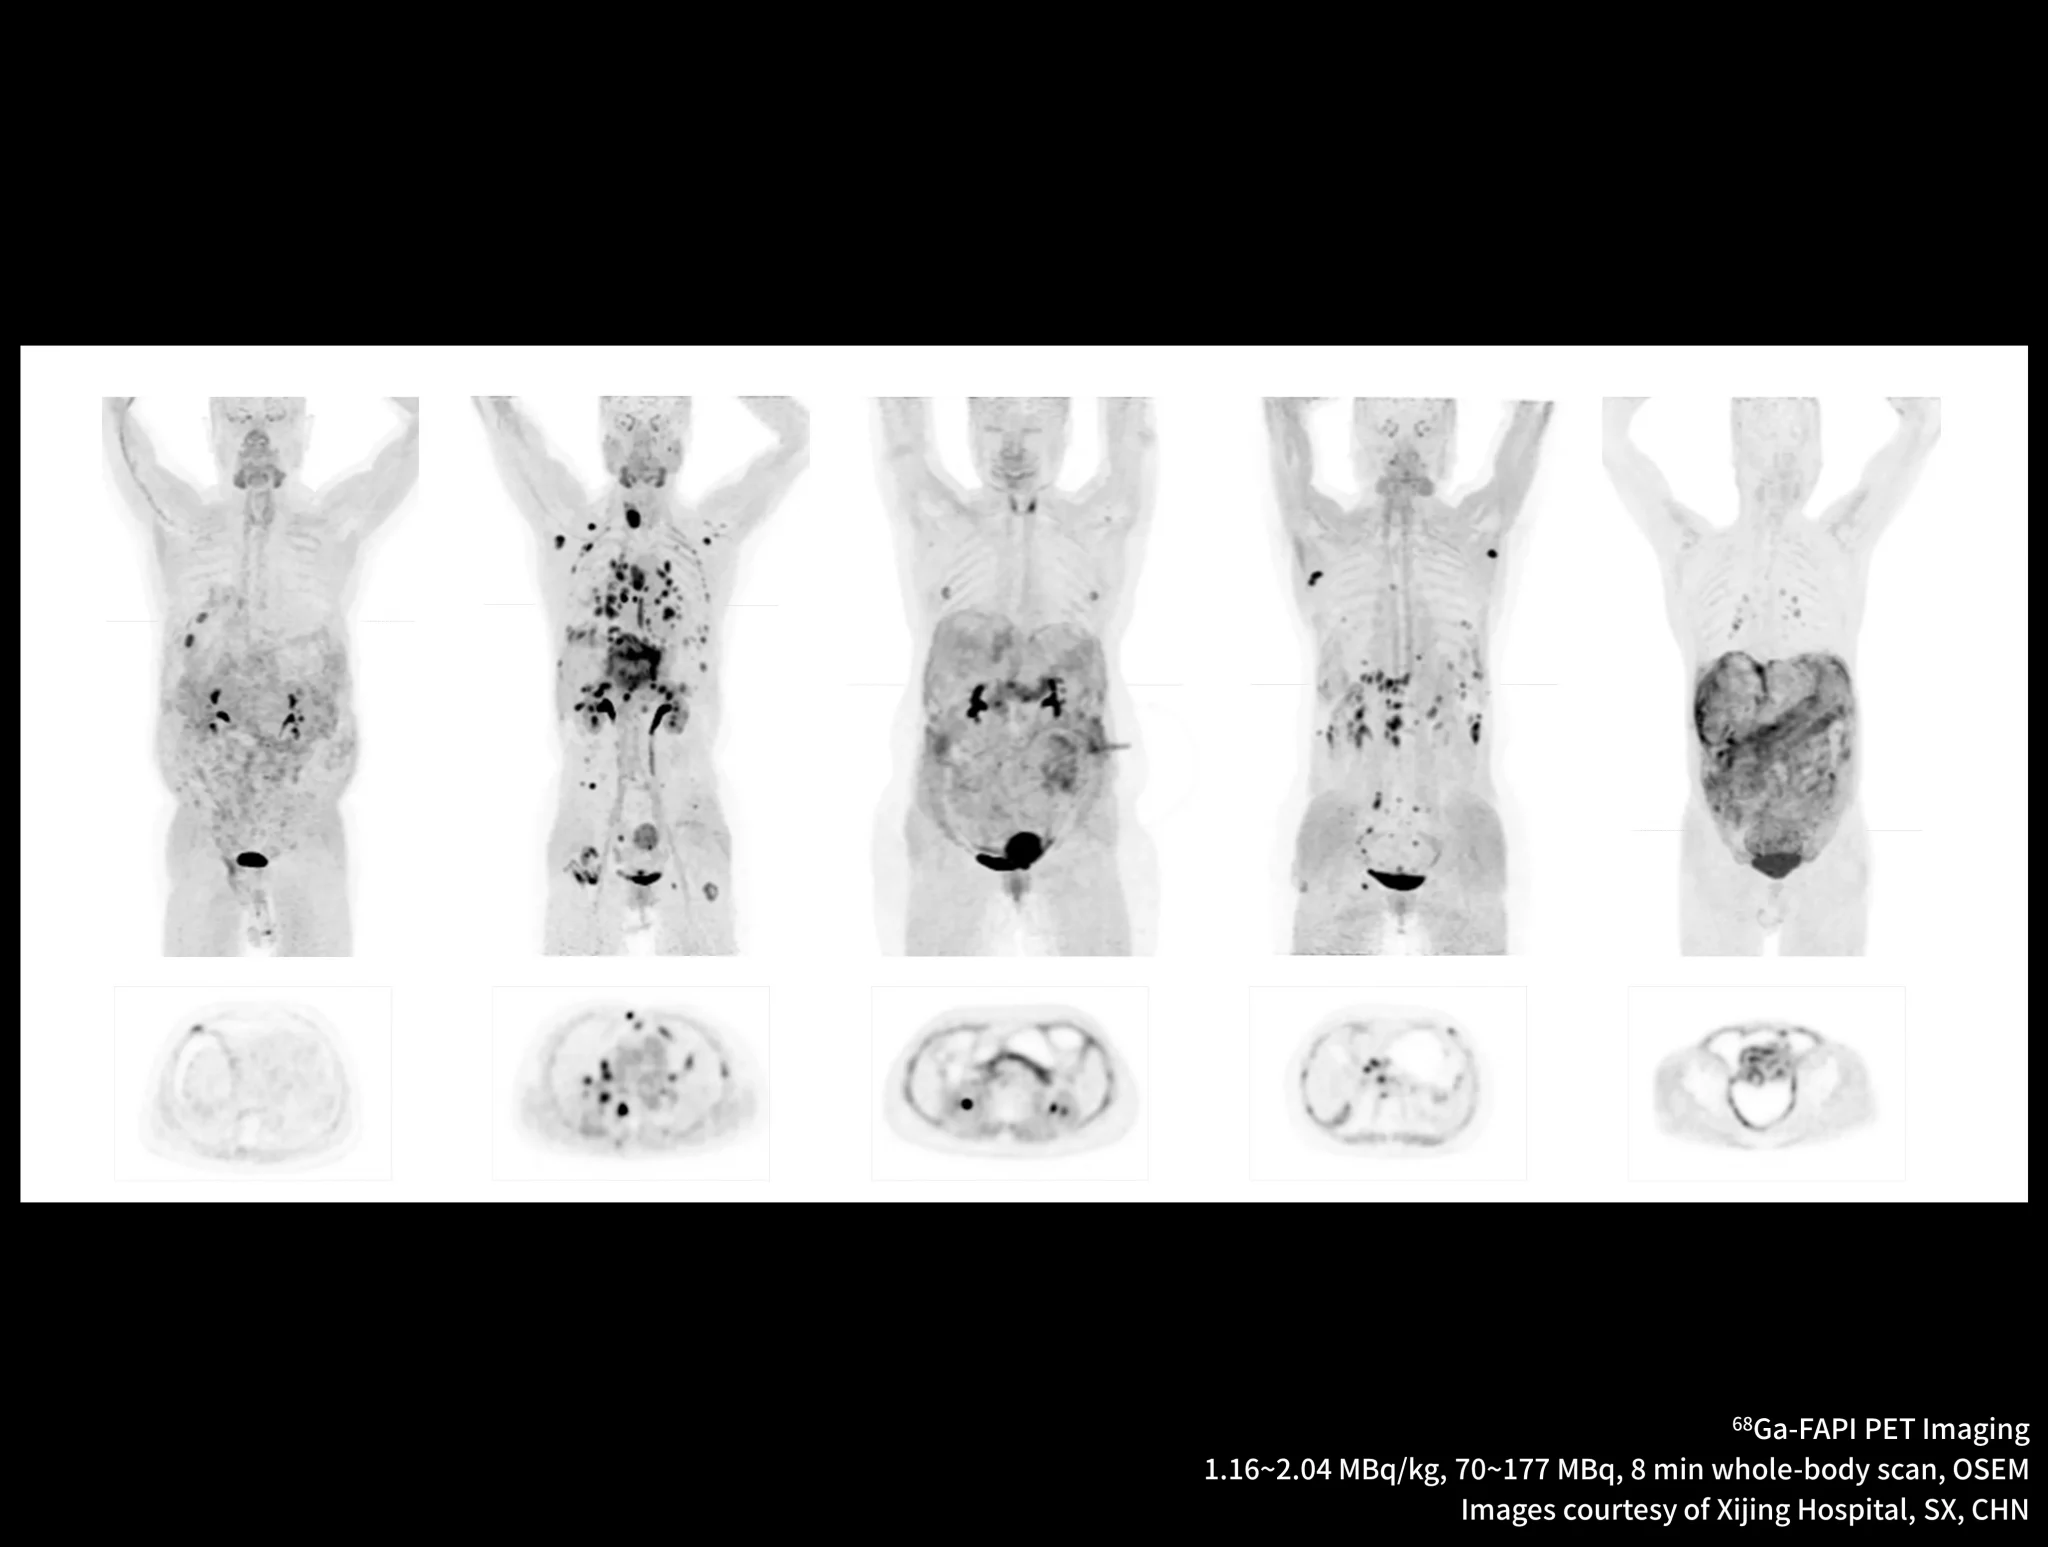

New-Tracer Imaging

Click on different tracers to see the images.